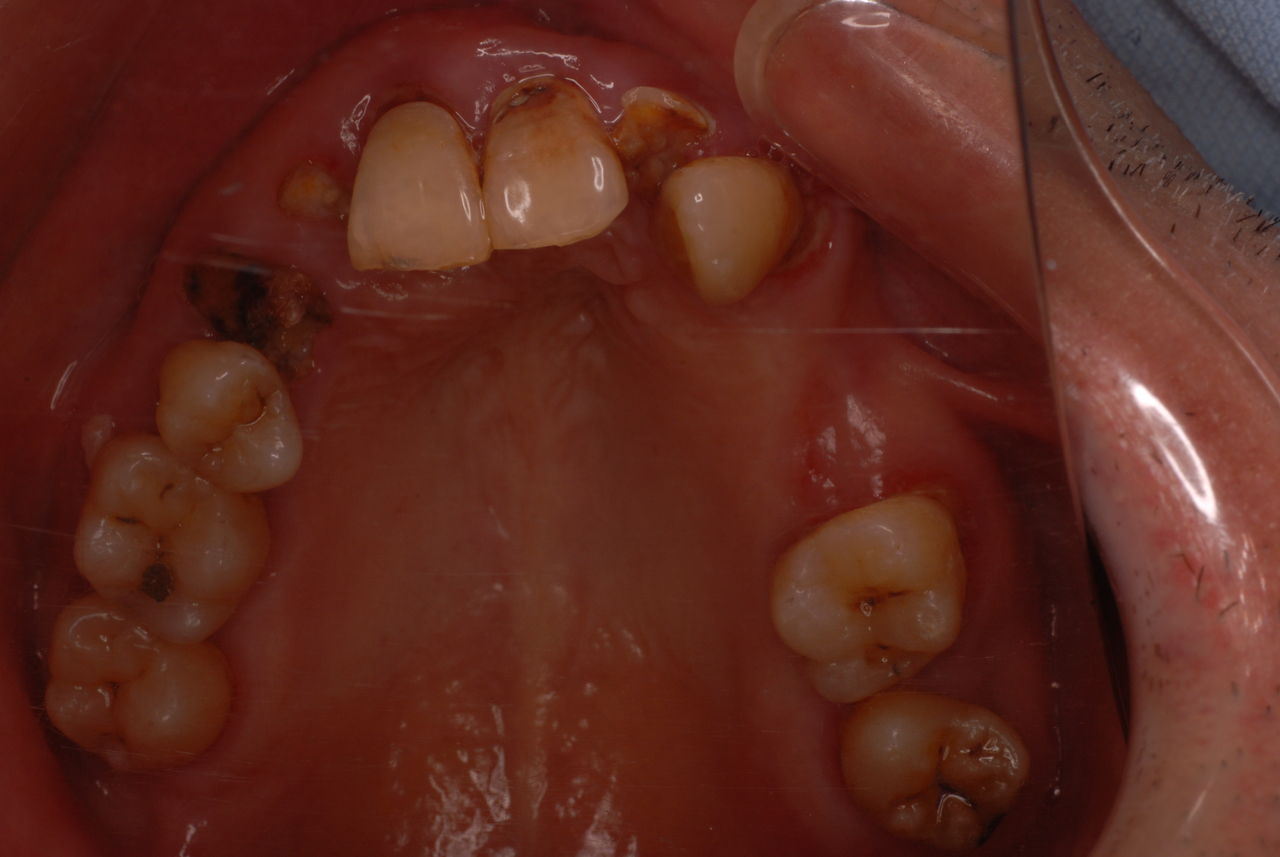

親知らずを取ることを嫌がる方が多いのですが、もし親知らずとその隣の14歳大臼歯の間に虫歯ができたり歯周病を罹患した場合、どれほど治療が大変で再発も起こりやすいか理解できない方がおおいのです。

写真左下の親知らずが痛くなり抜歯しました。その後歯茎を除去して虫歯を露出させる処置を二回ほどしています。

レントゲンでは小さいですが、こう言う虫歯が一番怖いのです。

治療の成功率は極めて悪くすぐ再発しやすいのです。